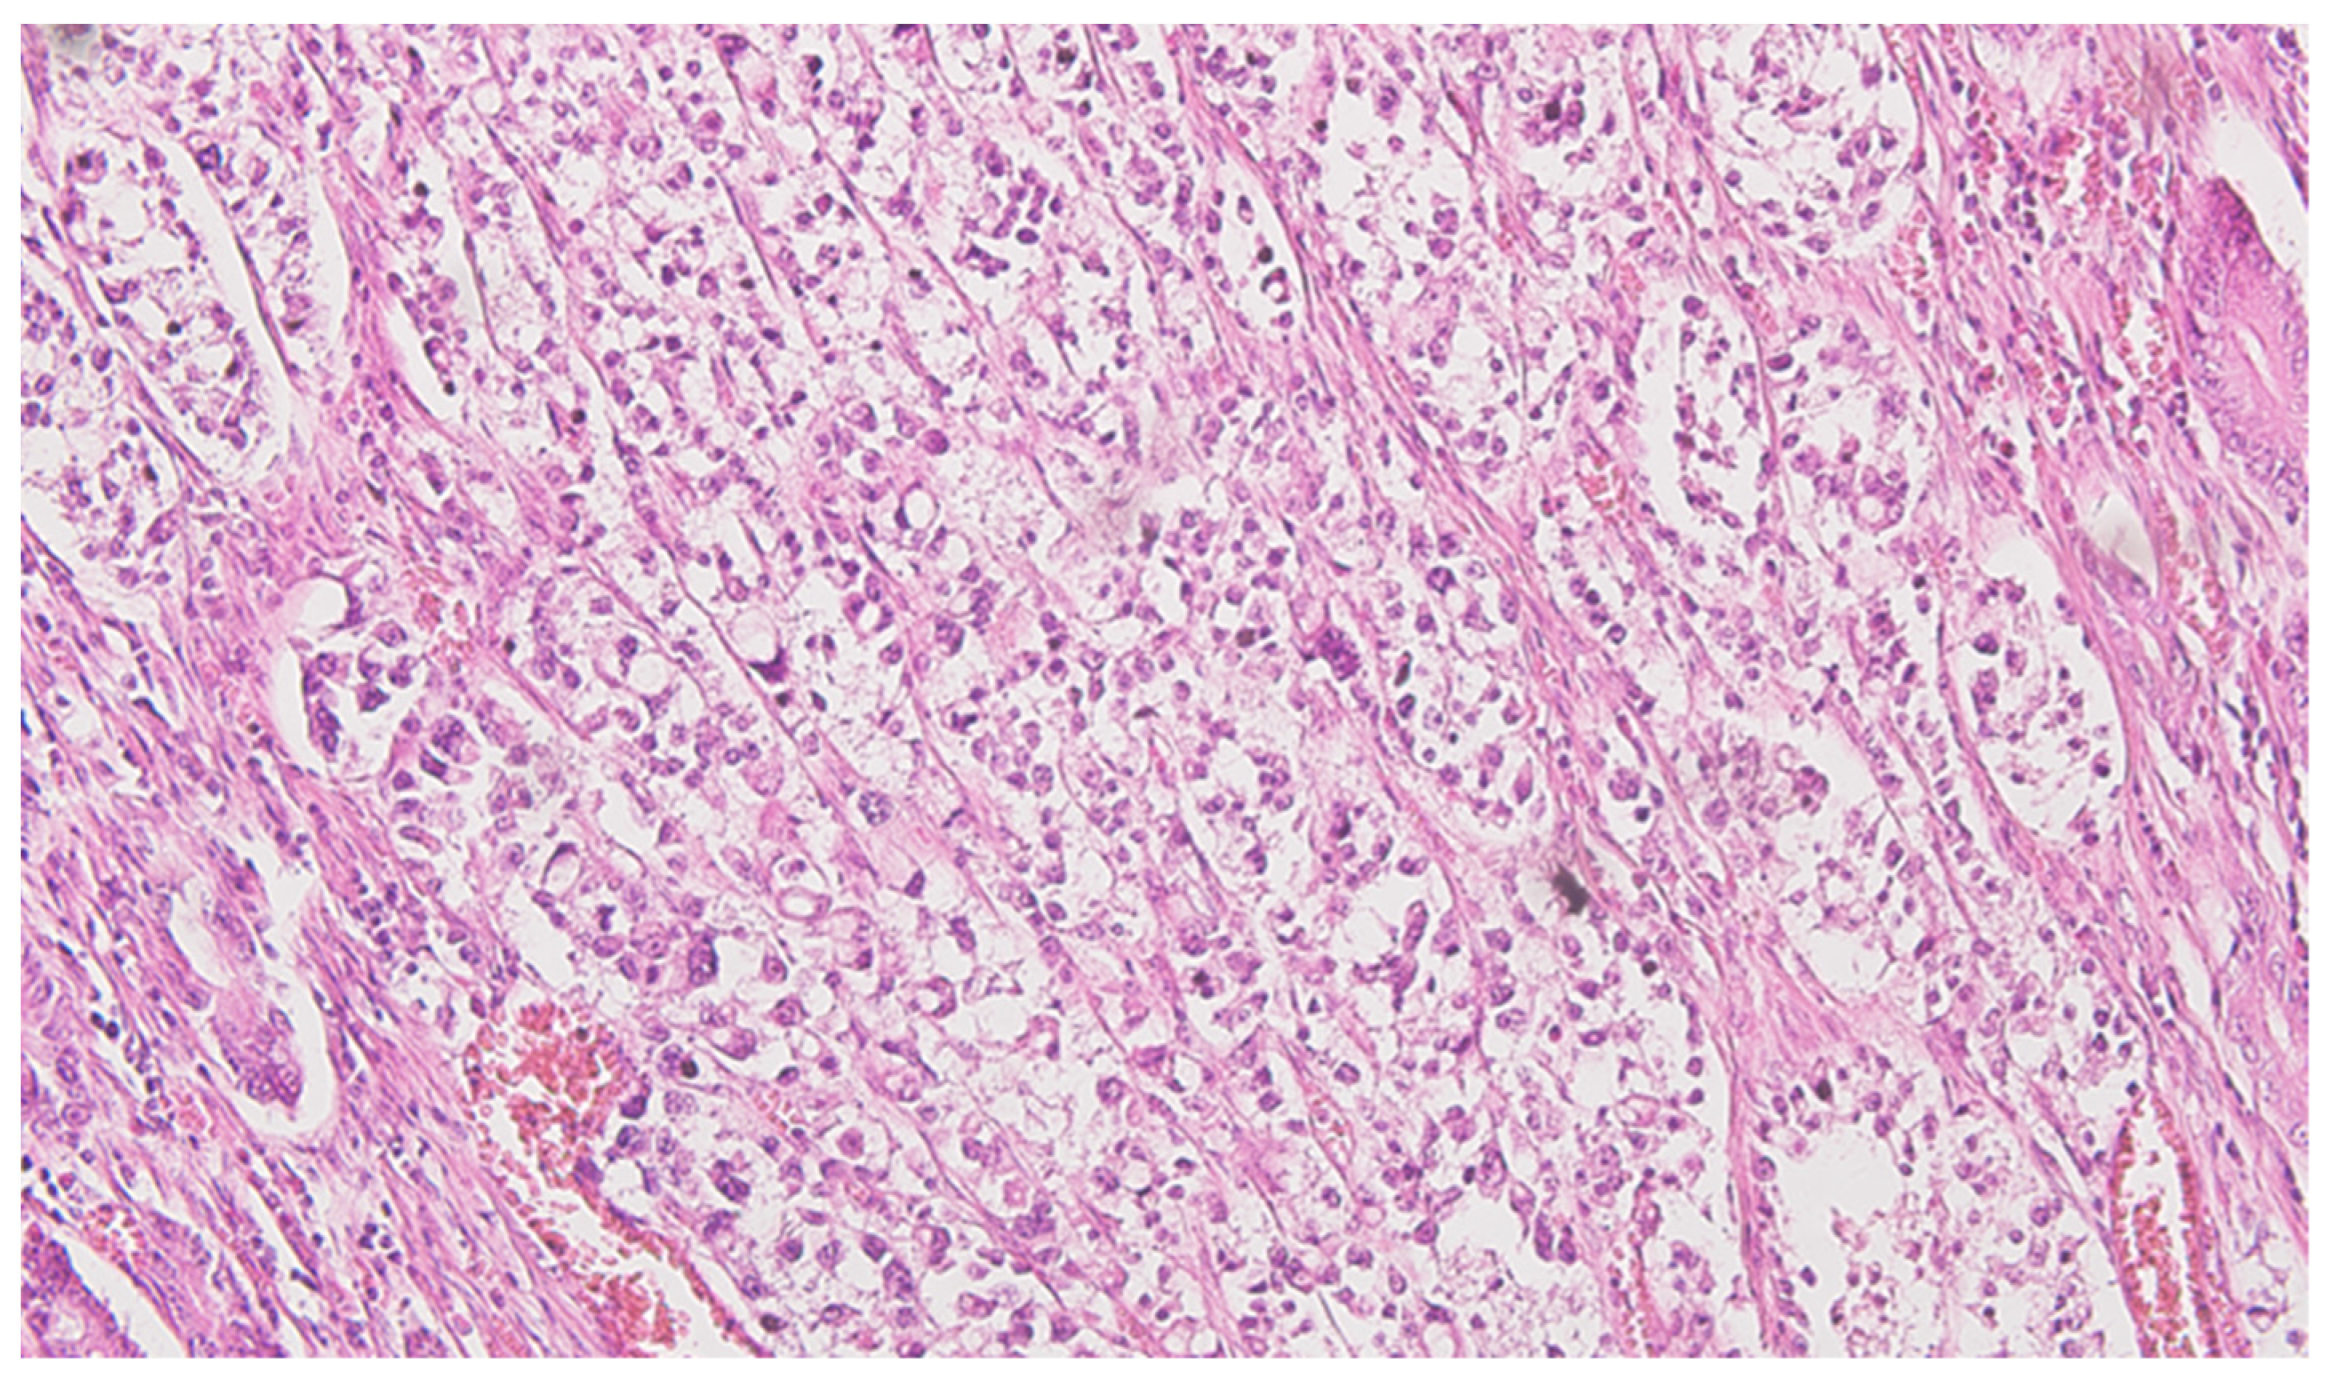

Serial sections of the ascending colon tumor reveal massive infiltration of a diffuse, mucinous carcinoma, with predominantly intracellular secretion of mucin (“signet-ring” cells); some isolated aspects of mucinous tubular adenocarcinoma are also observed. The tumor is ulcerated on the surface, extensively invades the submucosa (Figure 1), and dissociates the muscular layer (muscularis propria), being found massively in the subserosa (Figure 2), with perforation of the visceral peritoneum: tumor cells in ink or less than 1 mm from the inked serosa (pT4a); numerous lymphatic tumor emboli, with frequent aspects of perineural invasion. Of 26 lymph nodes, 24 show massive carcinomatous metastases (adenocarcinoma type, Figure 3)—pN2b.

Figure 1.

Colon mucinous carcinoma signet-ring colon carcinoma invading submucosa, HE ×200.